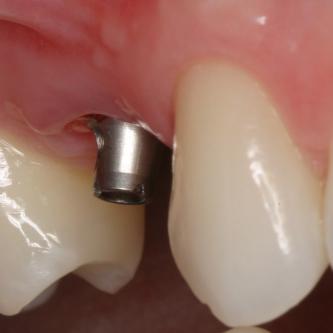

Exemple 3: Un implant à la place d'une incisive latérale supérieure droite. Sur cette image on voit le moignon en titane qui est vissé sur l'implant.

Exemple 3: Puis sur ce moignon, la couronne en céramique est scellée.